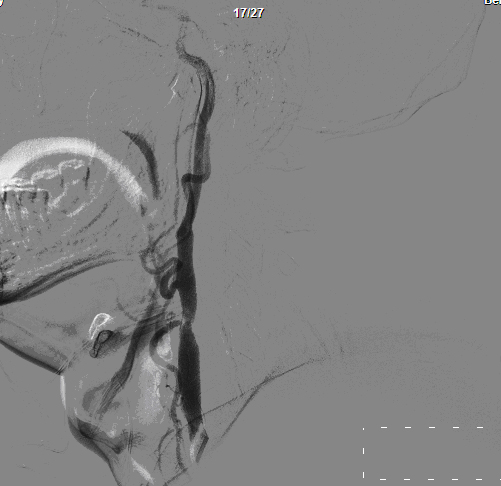

DSA:左侧颈内动脉重度狭窄

头颈动脉CTA:左侧颈内动脉开口处,管腔中-重度狭窄,双侧颈总动脉轻度狭窄,右椎动脉远端较对侧纤细;双侧大脑前中后动脉CT增强未见异常。